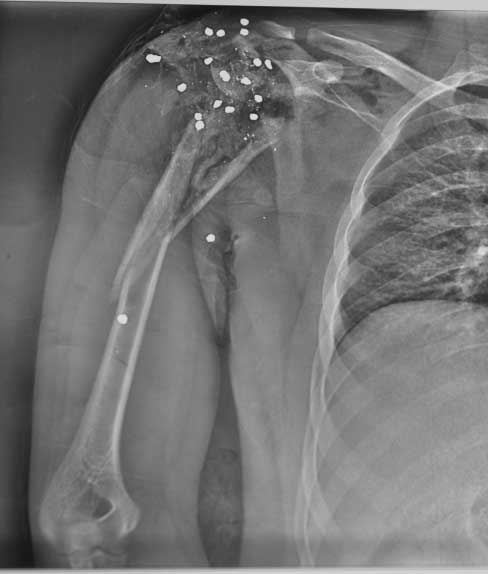

Молодой человек 25 лет поступил с огнестрельным ранением области плечевого сустава.

травма 12.05.12 - огестрельное ранение правого плечевого сустава, открытый многооскольчатый перелом проксимального отдела плеча с переходом на диафиз. стреляли практически вупор. Входное отверстие округлое диам 3 см по передней поверхности дельтовидной области, выходных отверстий множество диам до 0,5 см больше по задне верхней поверхности дельтовидной области. при поступлении - ПХО при ревизии - удален пластиковый пыж, повреждена вся дельтовидная мышца частично повреждены надостная подостная мышцы, капсула сустава разорвана в клочья,сухожилия ротаторной манжеты также разорваны в кашу, головка плеча - ее не было - просто костная каша в ране, кроме того выявлен перелом акромиона. гленоид практически не пострадал. Рана промыта нежизнеспособные ткани иссечены, костная крошка удалена. швы на рану, перелом стабилизирорван стержневым аппаратом. На сегодняшний день - рана без воспаления, заживление первичное. Движения в кисти, локтевом суставе в полном объеме. Вопрос к уважаемому сообществу - что делать? С уважением Леонид Пак